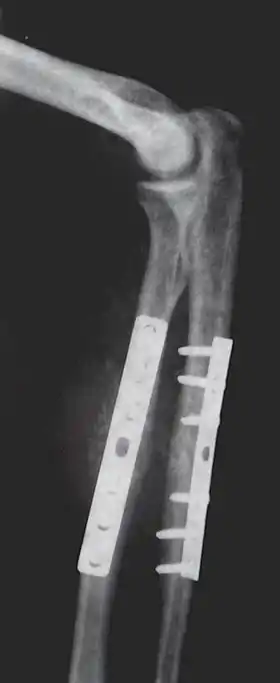

Orthopedic implants to repair fractures to the radius and ulna. Note the visible break in the ulna. (right forearm)

Anterior and lateral view x-rays of fractured left leg with internal fixation after surgery